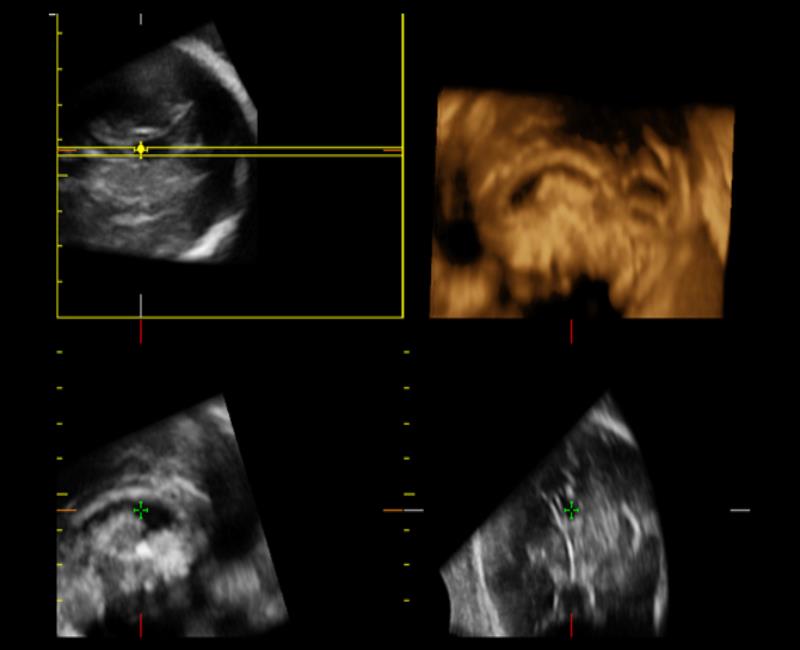

XLight - phần mềm siêu âm 3D/4D chuyên sâu cho mặt thai nhi mịn, chân thật nhờ công nghệ bố trí nguồn sáng ảo và khả năng tái tạo bề mặt.

may sieu am mylab x6

XLight với chế độ cột sống của thai nhi.